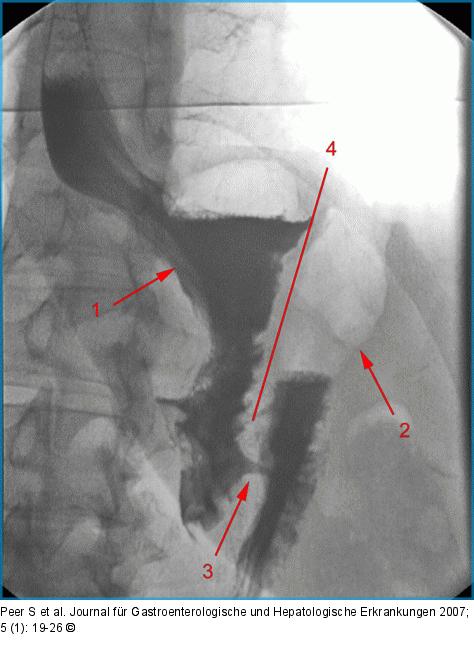

Abbildung 10: Magenband